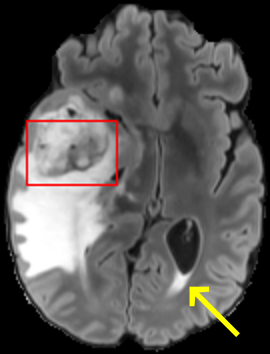

To test the impact of the iterative refinement on YODA’s translation quality, we compared regression and diffusion sampling on the RS data and present additional generation examples in Fig. 6. We observe that diffusion sampling visually resembles the appearance of the acquired images. Regression sampling preserves key anatomical features – the GM/WM boundary, WMHs (Fig. 4), the outline of the pallidum (Fig. 6) – but omits many high-frequency features. To investigate whether iterative refinement during diffusion sampling adds relevant and systematic medical information or only imitates acquisition noise, we performed ExpA sampling, i.e. averaging the output of several ( or ) diffusion trajectories. We observed a gradual loss of high-frequency details when increasing the (see also the supplementary video), indicating that the effect of the iterative refinement is non-systematic. For , the images are visually almost indistinguishable from the initial regression solution (see the supplementary video, and Fig.4 and 6). We directly compared the synthesis results of ExpA () and regression sampling quantitatively and found the differences to be minimal (SSIM: 99.73%, PSNR: 45.30 dB), i.e. diffusion sampling approaches the initial regression solution for a high . The quantitative analysis of the image quality (Tab. 1) showed that diffusion sampling impairs the assessed SSIM and PSNR in comparison to regression sampling for both the in- and external test sets, which we attribute to noise generation (Sec. 3.1). In turn, ExpA averages improved both metrics and, for , performed mostly on par with the regression solution in both test sets in terms of SSIM, while the PSNR in the RS was slightly increased (Tab. 1). However, we observed that ExpA sampling YODA improves the replication of systematic 3D low-frequency image intensity drifts (bias fields) due to the 3D synchronization in 2.5D diffusion sampling. Yet, this apparent advantage did not generalize to the external MBB dataset, as bias fields are MR protocol-specific.

We evaluated the impact of the proposed sampling methods on the performance of the independent, externally trained SHIVA-WMH tool as compared to manual reference labels (Tab. 1). Smoother images (higher or from regression sampling) yielded improved performance over those from diffusion sampling.

To assess the suitability of YODA-generated images for WMH detection independent of segmentation tools, we also calculated the CNR (15) of WMHs. This confirmed that the contrast of WMHs is preserved in the regression images, whereas we noted slightly reduced WMH contrast for diffusion and ExpA-sampled images (Tab. 1).

When analyzing the RS synthesis results (Fig. 4), we noted that most reference methods strive to imitate realistic images, but several artifacts can be observed such as hallucinated WMHs (SynDiff) and salt-and-pepper noise (SynDiff, I2I-Mamba, ResViT).

However, we observed some missing small WMHs (third row, Fig. 9) in the synthetic FLAIR images. Due to the weak input signal, translating small WMHs in inherently difficult and, thus, omitting these WMHs can be seen as conservative. In contrast, a more speculative translation bears the risk of false-positive, hallucinated WMHs (compare e.g., SynDiff, Fig. 4).